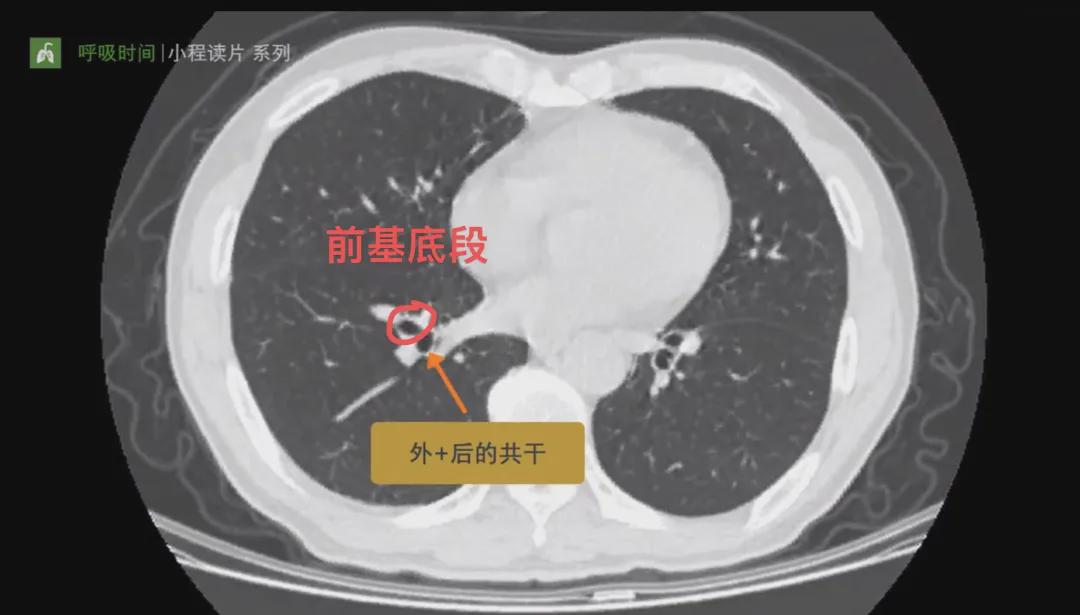

在CT横断面最先出现的是背段,其次是内基底段和右下叶支气管主干,肉眼在CT上看到的是两个孔。往下走主干分出两个孔,其中一个是前基底段,前基底段分出后,外基底段和后基底段公用一个孔,所以还是看到两个孔。